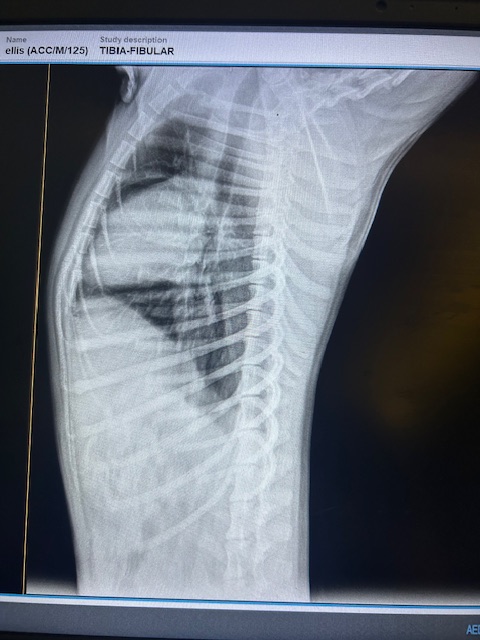

Wir wissen das die Chance jemanden für Lenny zu finden sehr gering sind, aber er ist so ein unglaublich liebenswerter und lebensfroher Hund, sodass wir ihm einfach diese Chance geben müssen... Als wir Lenny fanden, lag er hilflos am Straßenrand – kaum bewegungsfähig, schwer verletzt und allein. Alles deutete darauf hin, dass jemand mit einem Knüppel auf den kleinen Welpen eingeschlagen hatte. Er konnte sich nicht mehr bewegen, sein Blick voller Schmerz – und doch voller Hoffnung, als wir ihn aufnahmen. In der Klinik brachte das Röntgenbild die traurige Wahrheit ans Licht: Zwei Wirbel in seinem Rücken sind verschoben, vermutlich durch den Schlag. Die Folge – eingeklemmte Nerven, die seine Hinterbeine lähmen. Er kann sie nicht gezielt bewegen, streckt sie unkontrolliert von sich. Doch im Wasser sehen wir: Irgendetwas in ihm kämpft weiter, denn beim Schwimmen macht er Bewegungen – wenn auch steif.

Sammy-Sunshine ist ein junger Hund – noch ein echter Welpe, der voller Energie, Lebensfreude und Neugier steckt. Trotz seines schweren Starts ins Leben hat er seinen fröhlichen Charakter nie verloren. Er kam stark abgemagert und mit einer großen offenen Wunde an der rechten Körperseite zu uns ins Center. Unsere Tierärzte haben ihn sofort erstversorgt, und am nächsten Tag wurde er in der Top Vet´s Clinic geröntgt. Leider ergab das Röntgenbild eine schlimme Diagnose: Sammy hat ein gebrochenes Becken, das nicht operiert werden kann. Eine vollständige Heilung wird es also nicht geben.

Manche Geschichten lassen einen sprachlos zurück – Dropies ist eine davon. Gefunden haben wir sie bei einer unserer Kastrationsaktionen. Eigentlich wollten wir ihre Mutter mitnehmen, doch die Anwohner wehrten sich vehement – Kastration sei „haram“. Innerhalb von Sekunden wurde die Hündin verjagt. Und dann sahen wir Dropie: ein kleines humpelndes Hundekind, mitten unter ihren sechs Geschwistern. Der nächste Streit begann – diesmal um Dropie selbst. Wir wussten: wir können sie nicht zurücklassen. Zum Glück konnten wir uns durchsetzen und Dropie mitnehmen. Ihr Hinterbein war schwer verletzt – laut Anwohnern wurde sie von einem Auto überfahren. Doch niemand half ihr. Sie lag tagelang einfach dort, in ihrem Schmerz. In der Top Vet´s Tierklinik offenbarte das Röntgenbild das ganze Ausmaß: ein alter, komplizierter Bruch. Doctor Essam war ehrlich – eine Operation wäre schwierig. Aber wir wollten ihr Beinchen nicht einfach aufgeben. Leider blieb der Erfolg aus – die OP brachte nicht die erhofften Besserung. Doch Dropie ist eine Kämpferin. Sie nutzt ihr Bein, bewegt sich, spielt – und scheint, soweit die Ärzte es beurteilen können, schmerzfrei zu sein und nur das ist es was zählt. Eine Amputation ist weiterhin ein Thema, aber nur, wenn es medizinisch notwendig wird. Solange sie noch im Wachstum ist, beobachten wir die Entwicklung ihres Beines.

Lou wurde von Passanten gefunden, die uns zum Glück direkt anriefen. Man sah ihm auf den ersten Blick an, dass er starke Schmerzen hatte und genau diese Umstände machten es so schwer, ihn anzufassen. Wir gaben natürlich nicht auf und schafften es irgendwann, ihn vorsichtig in eine Box zu legen. So fuhren wir direkt zum Tierarzt, da wir wissen wollten, wieso er so starke Schmerzen hatte. Beim Röntgen kam raus, sein Becken ist gebrochen, wieso, weshalb, warum, wissen wir leider nicht. Nach einem Gespräch mit dem Doktor kam raus, es ist inoperabel. Er bekam Physiotherapie und langsam bauten sich seine Muskeln wieder auf. Die Schmerzen verschwanden.